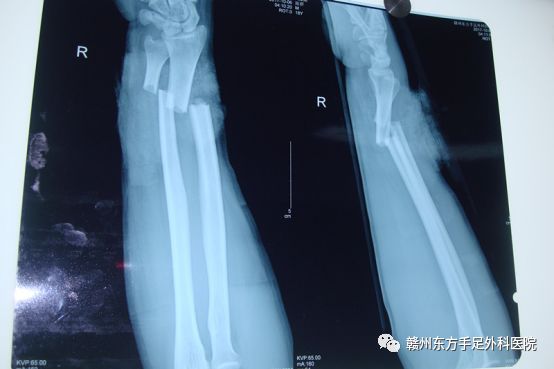

患者陈某,男性18岁,因2017.10.6晚上在街口被人砍伤右手前臂,来我院就诊,见右前臂远端畸形肿胀明显,尺背侧有一约5.0cm的横行创口,深达骨质,创缘较齐,出血活跃,创口内可见大量断裂的肌性组织及骨折断端外露,各指伸指功能丧失,末梢血运可,感觉麻木;腕关节活动受限。收入住院2017-10-06 05:00在李镍医师带领下、杨医生、王医生一起进行手术行:右前臂清创+尺桡骨骨折复位钢板内固定+上肢神经血管肌腱探查修复+VSD负压吸引术